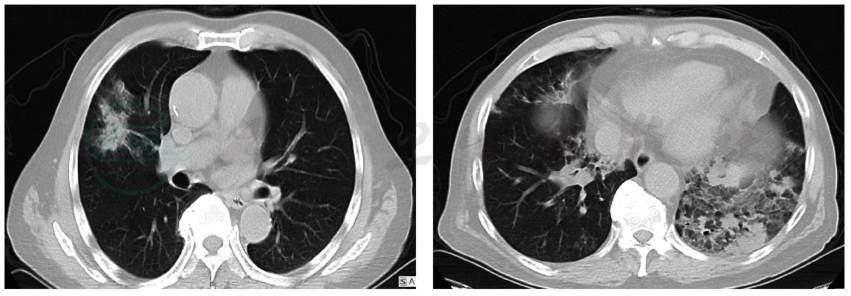

2017年5月4日肺部CT显示:两肺纹理增多,双肺多发斑片实变影,右肺上叶及左肺下叶为重(图1)。

图1 胸部CT表现:双肺多发斑片实变影,右肺上叶及左肺下叶为重